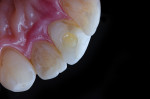

Next, tooth No. 9 was layered according to the strategic map. This is where a high degree of planning is combined with immediate feedback using a tethered digital camera to perfect the outcome and decision tree. First, a layer of composite (IPS Empress Direct Flow [Dentin A3.5], Ivoclar Vivadent) was placed at the gingival margin to prevent issues with crevicular fluids during the course of the appointment. Dentin shade A3 was applied next, extending 4.0 mm incisal to the zenith, over the fracture to 1.0 mm cervical and to the incisal edge in mamelon-like striations. This increment was thinned considerably near the incisal edge to create adequate depth for subsequent resin strata, characterizations, and effects.3,10,12 Dentin shade A2 was placed in the incisal third as vertical lobal highlights to increase the overall value and opacity. At this point, a macrophotograph was taken while the DSLR camera was tethered to a laptop for immediate visualization of the progression and fine-tuning of the strategy. It was noted that more opacity was needed at the incisal edge as well as horizontal striations in the cervical area. To accomplish this, an additional increment of shade A3 was added to the incisal third for increased opacity, and the A3.5 shade of the flowable was laced in horizontal striations in the cervical third using a brush and an explorer tine. Again, a photograph was taken to reliably check the refinements and position of each resin addition. White and ochre characterization materials (IPS Empress Direct Colors, Ivoclar Vivadent) were then added to recreate the white and amber highlights while preserving the mesial line angle and minor incisal edge translucencies. Each was placed with precision using an enlarged high-definition tethered progress image as a reference (Figure 11). Finally, an increment of the translucent opal composite was applied to the entire facial and interproximal surfaces of the restoration, refined with a brush and instruments, and light cured. At this stage, the vertical craze line could have been applied using a No. 12 scalpel blade; however, the last macrophotograph led the clinician to believe that because tooth No. 9 more closely matched tooth No. 10, teeth Nos. 7 and 8 would require 3 to 4 nights of external whitening in order to achieve perfect harmony in the esthetic zone. The patient reviewed the photograph with the clinician in real time and decided that he preferred the shade of teeth Nos. 9 and 10 to that of teeth Nos. 7 and 8 and wanted to proceed with bleaching treatment. Therefore, the decision was made to forgo the addition of the craze line and a high-gloss polish until the next appointment, and instead, a simple polish was performed with white, blue, and yellow polishing discs (Figure 12). The patient was sent home with a 16% carbamide peroxide bleaching gel (Kör-NightTM, KöR) and instructed to bleach every night then video call the clinician each morning. This call allowed the clinician to ascertain the progress on a daily basis and prevent the patient from whitening past the desired shade. Due to the effect that polishing has on microfills (ie, a subtle increase in value), the ideal shade for teeth Nos. 7 and 8 would be just slightly higher in value than tooth No. 9 was currently, if the patient could even achieve such a shade.13

After 3 nights of whitening, the patient and clinician were satisfied with the results and the increase in the overall value of the smile. Concomitantly, the clinician had studied the final images from the previous appointment (Figure 12) and noticed the need for a minor cutback to better adapt the gingival shade to the smile. Furthermore, because of the magnified highlights from whitening, some additional white chroma would be needed at the incisal edge of tooth No. 9. After a 0.2-mm cutback was made and the proper adhesive protocol was performed, the alterations and refinements were made and an image was taken to validate the placement and shade. Finally, a single layer of trans opal shade composite was overlaid, establishing the proper facial contours and prominence.

The midfacial, vertical craze line was added to tooth No. 9 by tracing a penciled replication with a No. 12 scalpel blade, and then a contouring and polishing protocol was followed (ie, white disc, blue disc, blue cup, yellow disc, pink disc, finishing with polishing paste [Enamelize™ Polishing Paste, Cosmedent], pink cup, buffing point, buffing wheel). After contouring and polishing, a thorough rinse was performed, and a final postoperative image was taken to validate and critique the final result, ensuring esthetic success and patient satisfaction.